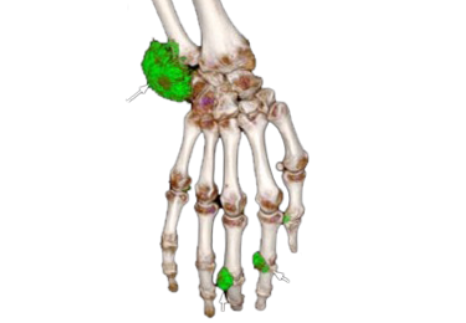

4X more urate deposits were found using DECT vs on clinical exam3